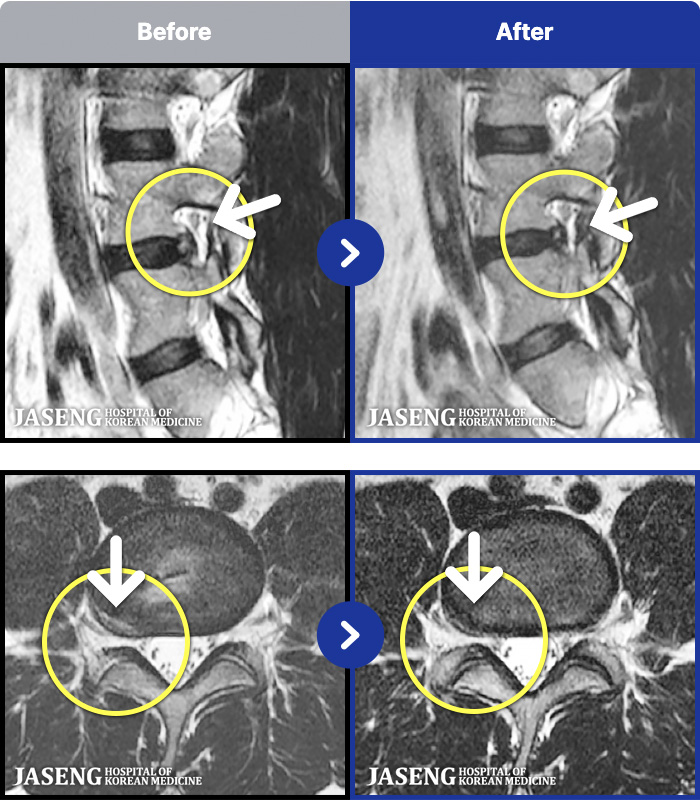

1,298 MRI ũ ʸ Ȯϼ.

[] 23.11.11~25.06.04